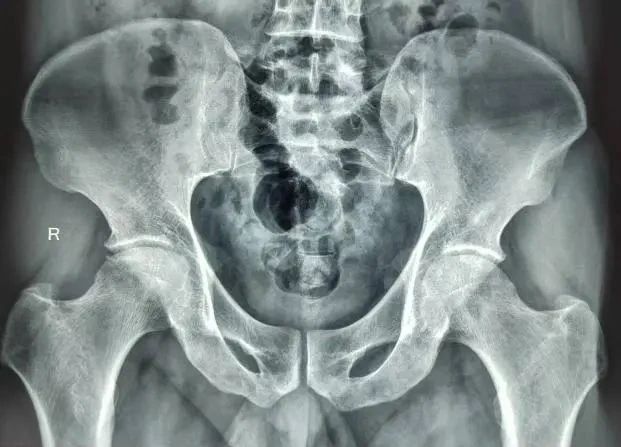

术前X光片